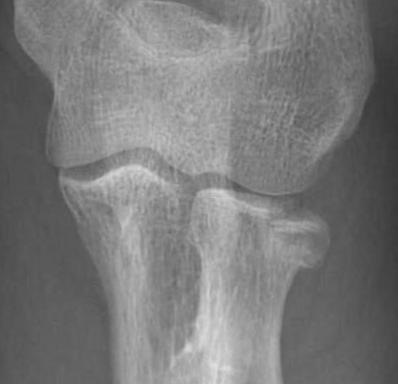

Hotchkiss modification of Mason Classification

Type 1: Undisplaced fracture / Intra-articular displacement < 2mm/ No mechanical limitation to forearm rotation

Type 2: Displacement > 2mm / Motion mechanically limited / Reconstructable

Type 3: Severely comminuted fracture / Non reconstructable

Type 4: Radial head fracture with elbow dislocation